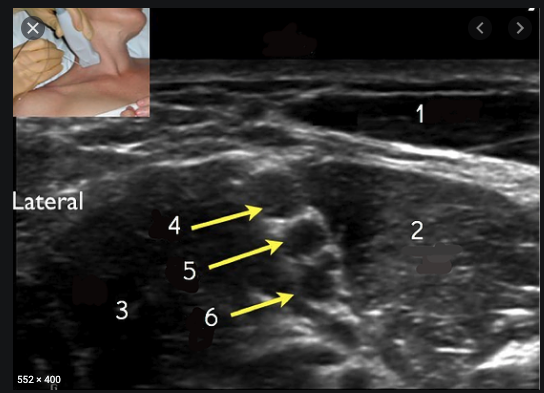

Identify the Block and Following Structures

Complications?